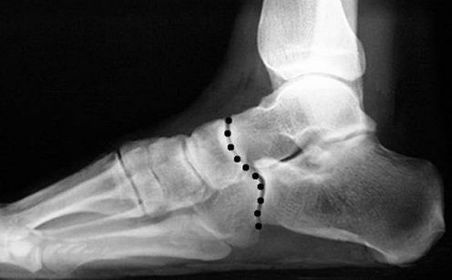

What is this called? What does an anterior break indicate? What does a posterior break indicate? | Cyma Line/Midtarsal joint. Anterior break = pronated foot type Posterior break = supinated foot type |